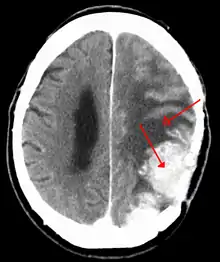

Meningiomata are visualized readily with contrast CT, MRI with gadolinium,[18] and arteriography, all attributed to the fact that meningiomata are extra-axial and vascularized. CSF protein levels are usually found to be elevated when lumbar puncture is used to obtain spinal fluid. On T1-weighted contrast-enhanced MRI, they may show a typical dural tail sign absent in some rare forms of meningiomas.[15]